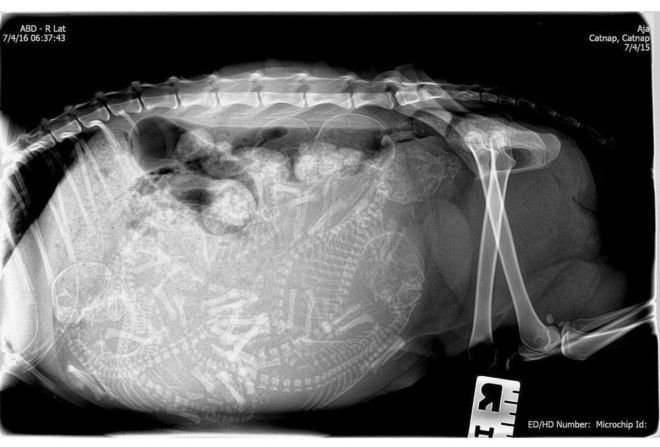

4. Еще одна кошка